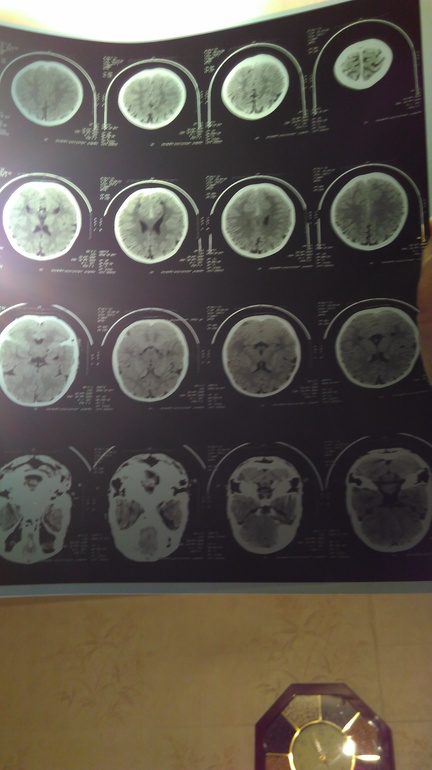

Так вот, невропатолог после обследования назначил нам КТ головного мозга и вот заключение:

КТ признаки открытой наружной гидроцефалии.